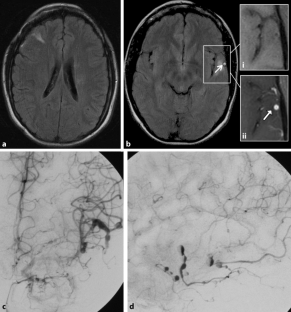

Abb. 2